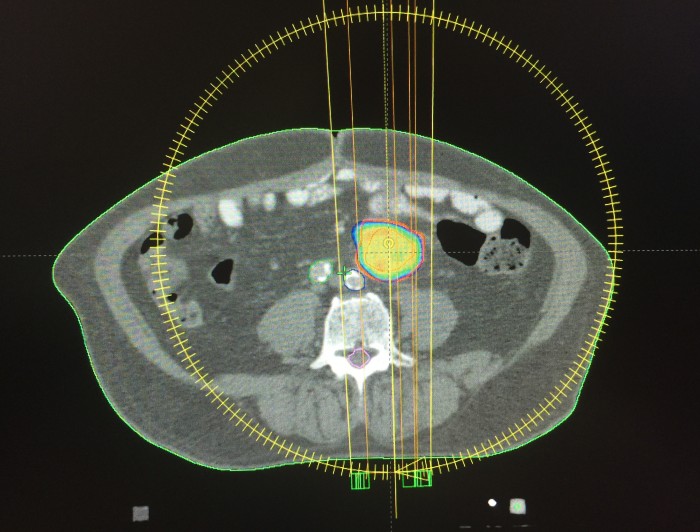

La radiocirugía extracraneal brinda precisión y exactitud, y requerirá la fusión de tomografías, resonancias y/o PET-CT, además de inmovilizadores adecuados, siendo indispensable la verificación diaria mediante imágenes pretratamiento para localizar el órgano blanco y poder administrar altas dosis de radiación focalizadas, respetando en lo posible los tejidos sanos circundantes.

La alta precisión, exactitud y conformación de dosis requeridas para garantizar la seguridad del paciente y poder administrar dosis tan altas en menos sesiones de las habituales, amerita un equipo humano y tecnológico precisos; sólo a manera de ejemplo: 1 sesión de SBRT de 24 Gy a un cuerpo vertebral metastásico equivale a 34 sesiones de 2.0 Gy.

SBRT en metástasis vertebral